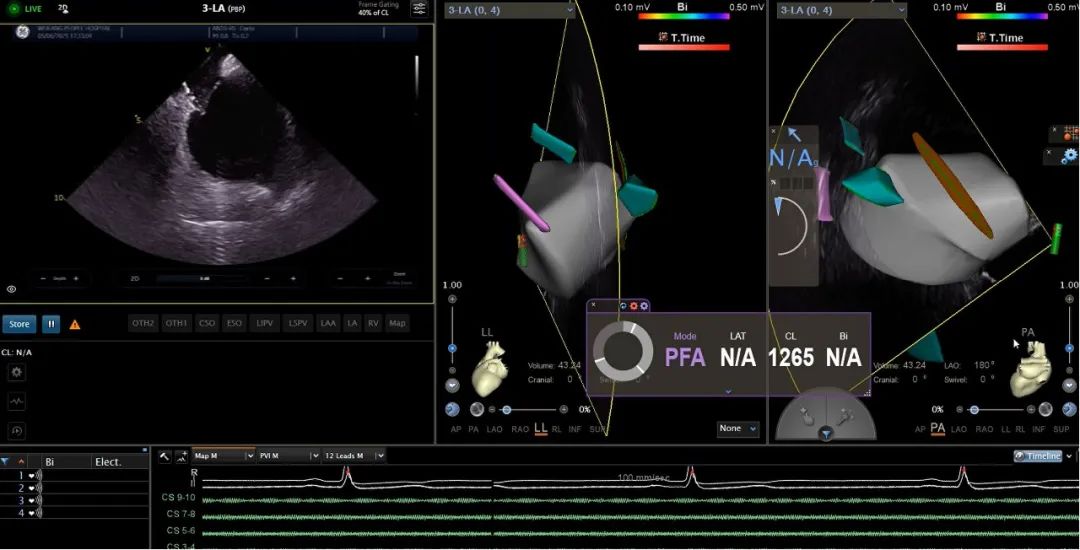

近日,潍坊市人民医院在陈彦波教授团队的带领下,成功完成全国首批VARIPULSE脉冲消融导管指导下的房颤消融手术。该技术通过三维电生理标测系统(CARTO 3)与脉冲电场消融(PFA)的深度整合,实现了房颤治疗的精准定位与安全消融,标志着我国房颤治疗正式迈入“三维可视化脉冲消融”时代。

术中数据显示,单台手术平均时间缩短至60分钟以内,肺静脉隔离时间仅8分钟/支,术中射线量为零,且患者术后恢复时间大幅缩短。

VARIPULSE可与CARTO系统无缝集成,全程三维可视,能够还原左房解剖,追踪消融损伤路径,帮助术者以更安心、高效的方式开展手术。它不仅能与心腔内超声(ICE)产品进行整合,提供实时成像,保障低/零射线手术的顺利开展,还可通过局部阻抗TPI显示电极与组织的贴靠程度,来确保有效放电。